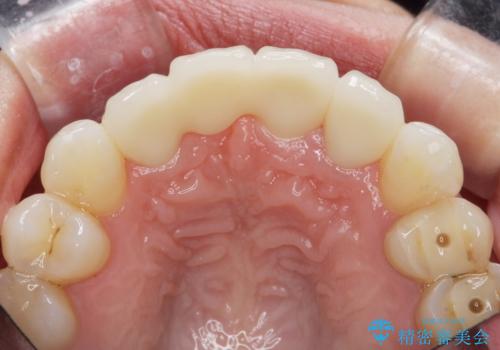

上顎4前歯は、根管治療の既往があり、虫歯も見られたことからブリッジによる治療で審美性の回復を行うとともに臨在歯の虫歯もセラミック治療を行っていきます。

- 44万円(仮歯・ジルコニアクラウン×4)費用は治療当時の料金となります

欠損部の歯ぐきの量が足りない場合は、移植を行い歯肉を増大させることもありますが、今回は仮歯で様子を見た結清掃性・審美性に問題が出なかったので行いませんでした。